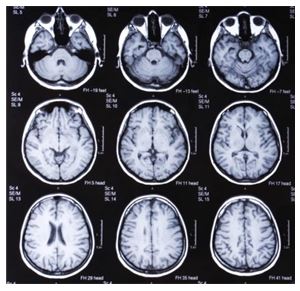

As we’ve been discussing, human brains expanded roughly by half between Homo erectus and modern Homo sapiens sapiens.

It’s hard to shake the norm that bigger is better; recent thinking in the area suggests that they are now shrinking in the relatively modern era.

“Over the past 20,000 years, the average volume of the human male brain has decreased from 1,500 cubic centimetres to 1,350 cc, losing a chunk the size of a tennis ball. The female brain has shrunk by about the same proportion. “I’d call that major downsizing in an evolutionary eyeblink,” (John Hawks) says. “This happened in China, Europe, Africa—everywhere we look.” If our brain keeps dwindling at that rate over the next 20,000 years, it will start to approach the size of that found in Homo erectus, a relative that lived half a million years ago and had a brain volume of only 1,100 cc.

While it’s getting smaller there is evidence this might be euphemistically called a refinement:

Recent studies of human fossils suggest the brain shrank more quickly than the body in near-modern times. More important, analysis of the genome casts doubt on the notion that modern humans are simply daintier but otherwise identical versions of our ancestors, right down to how we think and feel. Over the very period that the brain shrank, our DNA accumulated numerous adaptive mutations related to brain development and neurotransmitter systems—an indication that even as the organ got smaller, its inner workings changed. The impact of these mutations remains uncertain, but many scientists say it is plausible that our temperament or reasoning abilities shifted as a result.